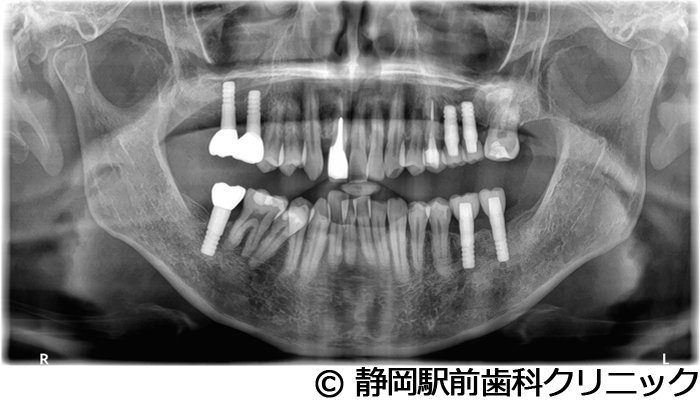

【症例5】全顎的インプラントとセラミックによる審美補綴

- 治療前

- 治療後

- 治療名

- 全顎的インプラントとセラミックによる審美補綴

- 費用

- 1,800,000円(税込)

- 期間

- 1年6ヵ月

治療内容

-

患者様の症状

全体的に歯がないため、噛めない。インプラント治療希望。

治療方法

全体的に残根は抜歯を行い、術前にCTを撮影し緻密に治療計画を立てた。インプラント埋入はブロックごとに行い、噛み合わせの調整を重ねた後、人工歯を被せて咬合と審美の回復を行いました。

治療結果

しっかり奥歯で食べ物を噛み切ることができるようになり、何でも食べることができるようになったと喜んでいただくことができました。口元を気にせずに笑うこともできるようになり、見た目もキレイになったとご満足いただけました。

※治療結果は個人差があります。

治療を行う上での注意点(リスク・副作用)

術後は、出血、腫れ、痛みなどが出る可能性があります。